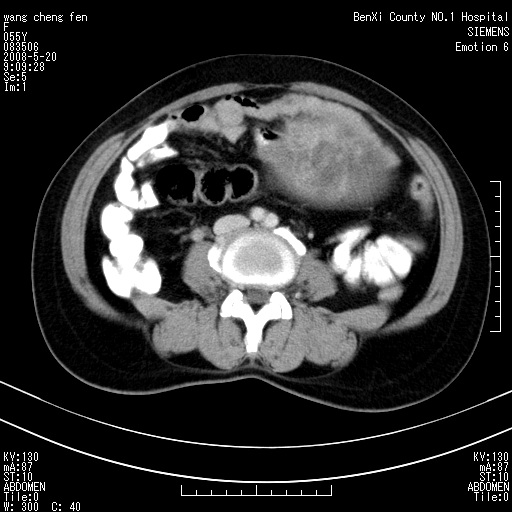

左侧附件区可见一囊性占位,边缘清楚,内可见不规则形软组织影 ce:囊壁及内部可见强化 考虑 卵巢囊腺瘤

左侧附件区巨大囊实性病灶,边缘光整,病灶囊壁较厚,增强示囊壁及实性部分明显强化,强化呈度与宫体实质大致相同,宫腔积液征像,未见盆腔积液等其他异常,考虑左侧卵巢囊腺癌,不除外囊腺瘤及浆膜下肌瘤坏死

左侧附件区巨大囊实性病灶,边缘光整,病灶囊壁较厚,增强示囊壁及实性部分明显强化,强化呈度与宫体实质大致相同,宫腔积液征像,未见盆腔积液等其他异常。绝经后阴道流血3个月,结合病史左侧卵巢囊腺癌首先考虑,宫腔扩大不除外累及。期待结果。

囊实性肿块分隔厚度较大,厚薄不均,增强实性成分明显强化,有不规则阴道流血,卵巢囊腺癌可能性大。